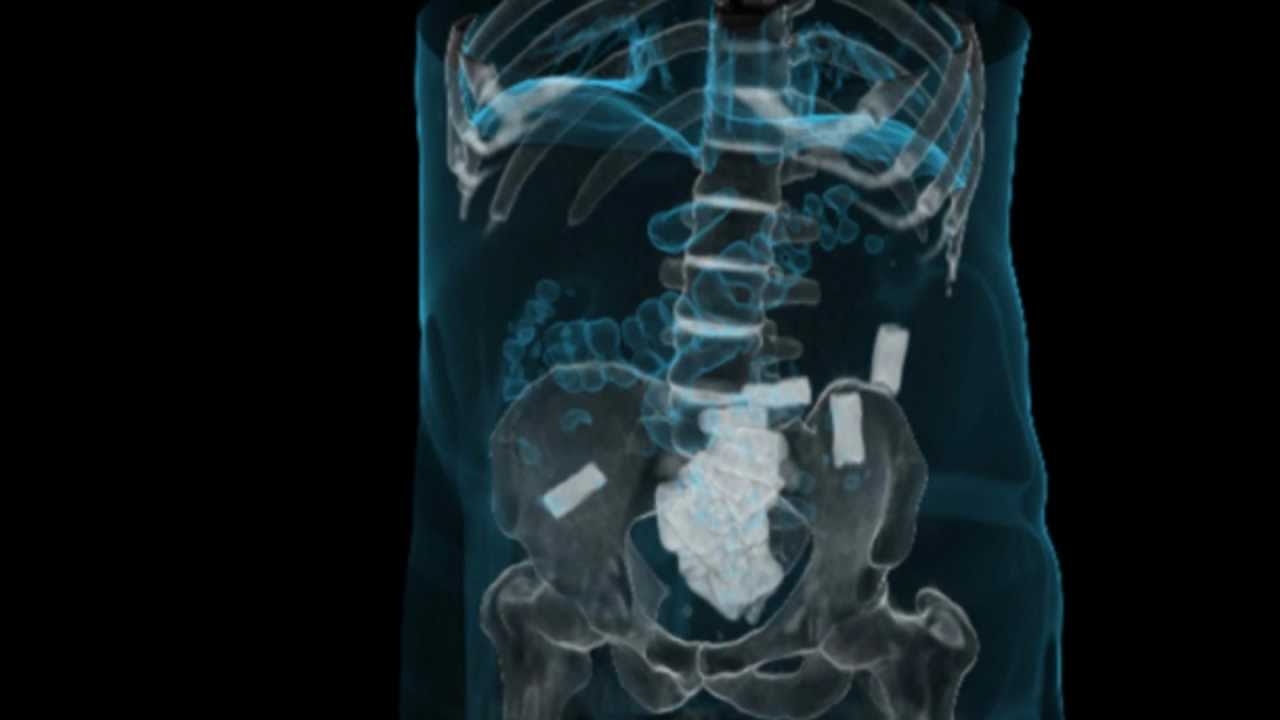

Así se ven las cápsulas de cocaína a través de placas.

Las primeras mulas introducían por estómago, vagina o ano droga en estado sólido, que era detectada a través de la realización de placas.

La modalidad de tráfico fue cambiando y exigió, a su vez, nuevas prácticas médicas para detectar la droga y salvar la vida de estos pacientes en riesgo: las cápsulas líquidas no son detectadas por placas, sino que solamente se ven con la práctica de tomografías computadas.